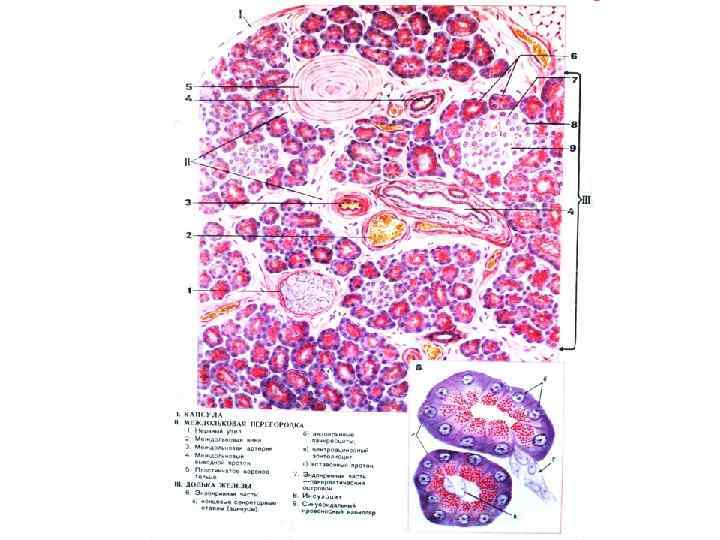

ПОДЖЕЛУДОЧНАЯ ЖЕЛЕЗА

Межацинарный проток

Ацинус и вставочный проток поджелудочной железы

Панкреатический островок А клетки – глюкагон В-клетки – инсулин D-клетки – соматостатин D 1 -клетки – вазоактивный интестинальный пептид РР-клетки - панкреатический полипептид

Препарат № 139 «Поджелудочная железа»

Вставочный и межацинарный протоки поджелудочной железы

Междольковый проток поджелудочной железы (однослойный эпителий)

Пластинчатые тельца

Зимогенные гранулы